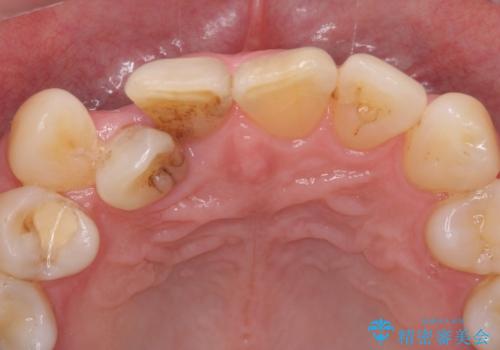

- 歯ぎしりでナイトガードが壊れたとの事で来院。

以前使用していたナイトガードは保険のものでした。

保険のナイトガードよりも強度があり、適合も良い自費のナイトガードのご案内をしました。

ナイトガードを使用することで歯のすり減り防止や歯の破折、被せ物の破折を防いでくれます。歯の寿命を伸ばしてあげるために日々ナイトガードを使用することをお勧めします。